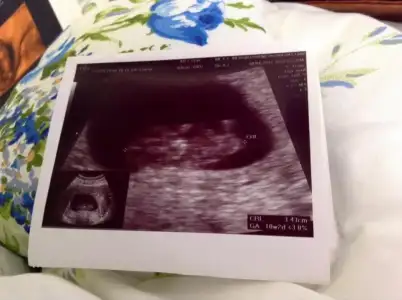

dr soylemeden siz gorun genital nub teorisi ( bebegin cinsiyeti)

$100_0199.webp Burda 12. haftamızı bitiriyoruz doktoromuz cinsiyetini görmüs ama heyecanlı olması için haftaya söyleyecek.öğrenince yazarım.

12+2 olduk bu gün teyzesi doktorumuz görmüs ama haftaya söyleyecekmis heyecanlı olsun diye :) ben ölüyorum meraktan haberi yok :))) siz tahminlerinizi yapın c.tesi kontrol sonucunu yazcam zaten.:emir_bebek: